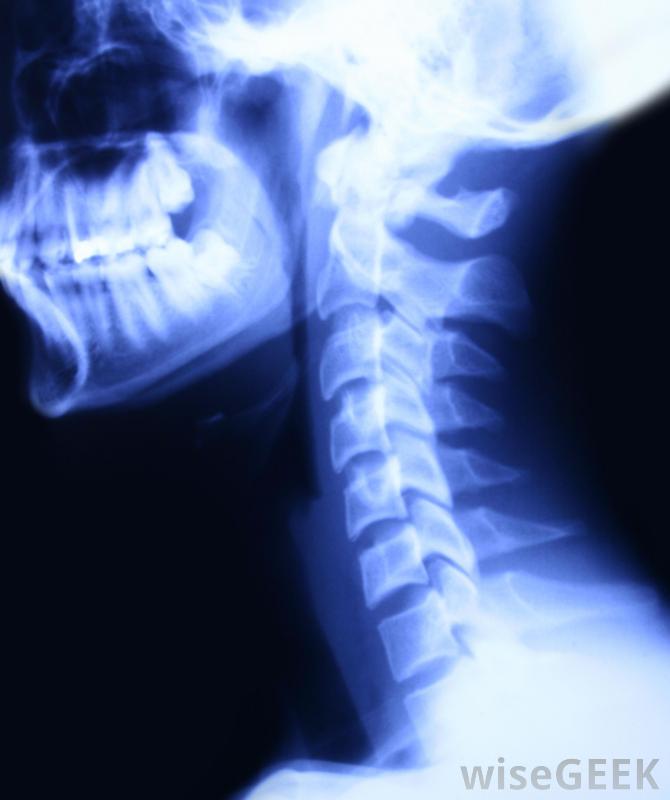

头骨的x光片这一领域的员工可以期待各种不同的工作环境,有时必须在压力下工作,有时在重病或痛苦时承受压力。这不仅有助于在你的领域进行培训,也有助于理解你的工作目标,创造问题的图景,尽管解决问题并不总是可行的,但是x光技术员在医疗保健的诊断方面起着至关重要的作用。

牙科X光片X光技师,通常被称为放射技师,使用诸如X射线机之类的设备来拍摄患者骨骼或其他内部部件的图像;牙科患者有时需要x光片。